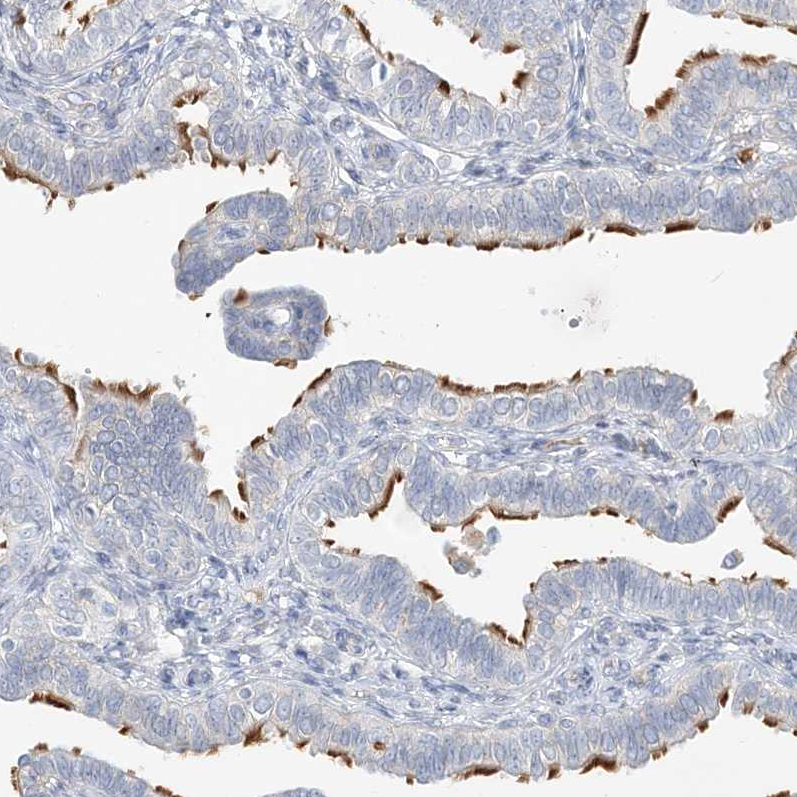

Immunohistochemistry analysis in human fallopian tube and liver tissues using HPA037470 antibody. Corresponding DNAH5 RNA-seq data are presented for the same tissues.